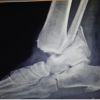

A detailed history was recorded for each patient, including the mechanism of injury, comorbid conditions, and prior treatments. A thorough clinical examination was conducted, with special attention to the vascular and neurological status of the affected limb. Radiographic evaluation included anteroposterior and lateral X-rays of the tibia and ankle to assess the fracture pattern, comminution, displacement, and intra-articular extension. Open fractures were graded according to the Gustilo-Anderson classification.

In this prospective observational study, we compared the functional outcomes of surgical and conservative management in patients with distal tibia shaft fractures. A total of 70 patients were enrolled in the study, with a predominance of males (55.7%) over females (44.3%). The age distribution was skewed toward younger adults, with 35.7% of patients falling within the 30–39 years age group. The majority of fractures were caused by road traffic accidents (64.3%), followed by falls (25.7%), and other causes, such as assault or heavy objects (10%). In terms of fracture type, 54.3% were closed fractures, while 45.7% were open fractures. Among the open fractures, Grade I was the most common (46.9%), followed by Grade III (31.3%) and Grade II (21.9%) (Table 1). Regarding the treatment modalities, a large proportion of patients (92.9%) underwent surgical management, with IMN being the most commonly used technique (46.2%). Other surgical interventions included minimally invasive percutaneous osteosynthesis (MIPO) in 30.8% and external fixator application in 23% of cases. Only 7.1% of patients received conservative management, reflecting the general preference for surgical intervention in these cases (Table 2). In terms of post-operative pain severity, the patients who underwent tibial interlock fixation experienced a gradual reduction in pain over time. At 6 weeks, 10 patients reported no pain, while 14 experienced mild pain and 5 had moderate pain. By 12 months, the majority of patients (25) had no pain, with only 3 reporting mild pain. Similar trends were observed in the MIPO and external fixator groups, although the incidence of pain was higher at the 6-week follow-up in these groups compared to the tibial interlock group (Table 3). Weight-bearing status also improved over time in all surgical groups. At 6 weeks, only 15 tibial interlock patients were able to bear partial weight, and no patients in the external fixator group could bear full weight. By 12 months, the vast majority of tibial interlock (25) and external fixator (25) patients were able to bear full weight. The MIPO group showed a similar improvement, with most patients bearing full weight by 12 months (Table 4). The radiological union was assessed at various follow-up points. At 3 months, 20 tibial interlock patients and 10 MIPO patients had a union in one cortex, while the remaining patients had a union in two or more cortices. By 12 months, union in at least one cortex was achieved in all patients, with more than half achieving union in two cortices in both groups (Table 5). Post-operative complications were noted in the surgical groups. The most common complications in the tibial interlock group were superficial infections (7 patients) and non-union (5 patients). In the MIPO group, 5 patients developed superficial infections, and 3 patients experienced non-union. No complications were reported in the external fixator group (Table 6). Finally, the final functional outcomes, assessed by the Johner and Wruhs criteria, showed a significant difference between surgical and conservative management. The tibial interlock group had the highest number of excellent (16) and good (10) outcomes, while the MIPO group also had a relatively high proportion of excellent outcomes (12). The external fixator group had a greater proportion of fair and poor outcomes compared to the other groups. Overall, surgical management led to a higher proportion of excellent and good outcomes (55%) compared to conservative treatment, which had only 7.1% of patients achieving good outcomes (Table 7).